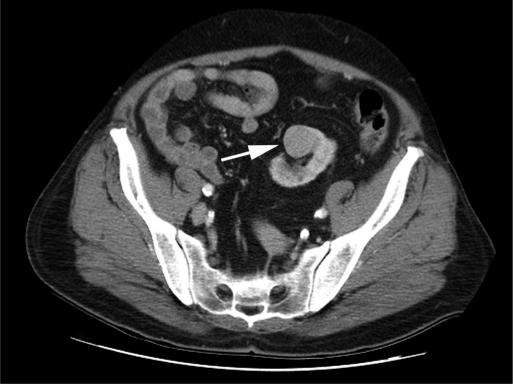

A 64-year-old male with a history of end-stage renal disease was diagnosed with a 2.6-cm enhancing mass in a pelvic left kidney with 2 separate sources of blood supply. He was offered either an open radical nephrectomy or a laparoscopic radical nephrectomy and opted for the minimally invasive approach.

The procedure was performed successfully without complications and with minimal blood loss. The case was marked both by difficulty in mobilizing the sigmoid colon and the limited working space of the pelvis, which made localization of the numerous hilar vessels challenging.

Laparoscopic radical nephrectomy for a pelvic ectopic kidney appears to be safe and efficacious. Success is dependent on familiarity with pelvic anatomy, optimal port placement, and preprocedure knowledge of the often-complicated vascular anatomy of the ectopic kidney. Preoperative imaging to delineate anomalous vascular anatomy is mandatory, and ureteral catheter placement is helpful for intraoperative identification purposes.